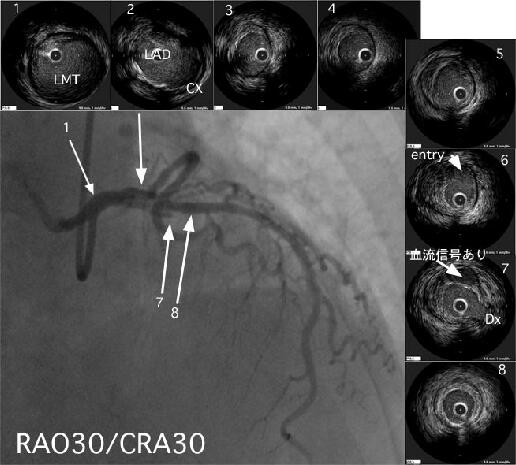

�A���M�I��IVUS���Î~�摜�݂̂Ȃ̂ŁA���(�ǂ݈Ⴆ)���Ă��邩������܂��A

IVUS4��LAD�̂ق�just-proximal�t�߂ł���ˁA�ŁAIVUS8��Dx��distal�ł���

�ˁBIVUS6�͖��炩�Ɍ��nja(EEM)��prox���傫���Ȃ��Ă��܂����(���Ȃ�positive-

remodeling)�B�����IVUS6�ł�plaque rupture�̔����k�̎����9���`12���t�߂ɂ�

lipid-pool�Ǝv����soft-plaque����������Ǝv���܂�(IVUS7�̂W���`11����)�B

IVUS6�ł́A���炩��fibrous-cup��F�߂��Alumen�ƌ�ʂ��Ă���悤�Ɍ����A���̔�

���k(cavity)���AIVUS7��Dx�̕��܂ő����āA���̕t�߂ŃA���M�I���IVUS�����~

�܂��Ă���l�Ɍ����܂��B�搶����w�E��distal�̒f�[�ł����AIVUS8�ł́A�قƂ��

lipid-plaque���Ȃ����߁Acavity���������āh�s�p��cavity�h�Ɍ����Ă���̂ł͂Ȃ�

�ł��傤���H